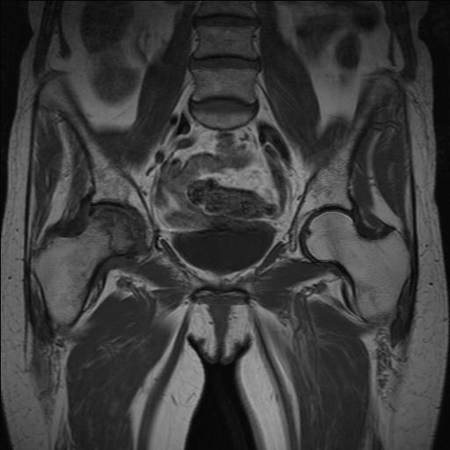

La patología del labrum puede ser un hallazgo incidental.[Figure caption and citation for the preceding image starts]: IRM que muestra una fractura por sobrecarga en el cuello del fémur derecho inferior (lado de compresión)De la colección de Cedric J. Ortiguera, MD [Citation ends].

[Figure caption and citation for the preceding image starts]: IRM que muestra osteonecrosis en la cabeza del fémur derechoDe la colección de Cedric J. Ortiguera, MD [Citation ends].